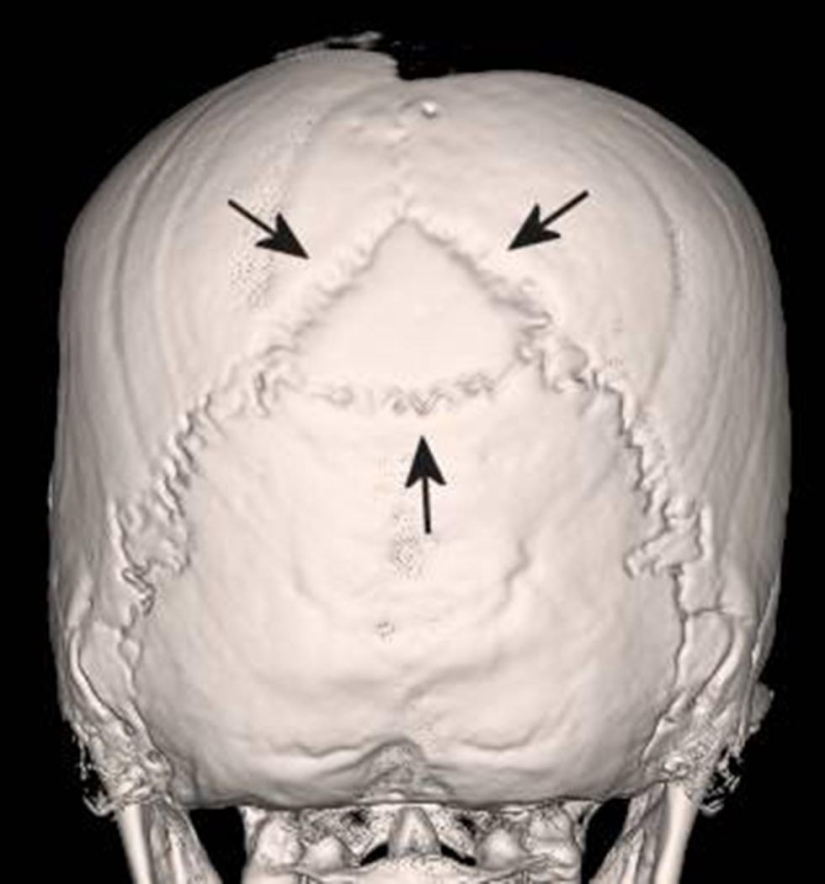

Una radiografía del cerebro de una niña de 15 años muestra que hay una separación entre la materia blanca y gris del cerebro. Las flechas apuntan al aire que rodea el cerebro.